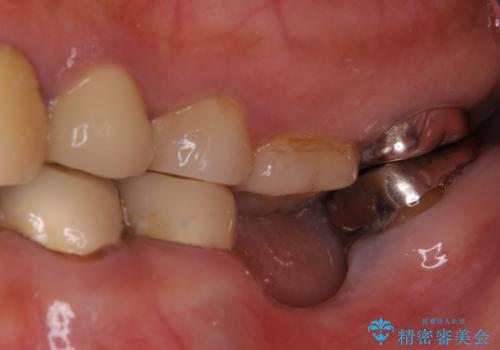

[重度の骨吸収] 顎骨の再建を伴うインプラント治療

![[重度の骨吸収] 顎骨の再建を伴うインプラント治療の症例 治療前](https://seimitsushinbi.jp/wp/wp-content/uploads/2019/05/e9019076b1821eb07ff5f43054741ecb-500x350.jpg)